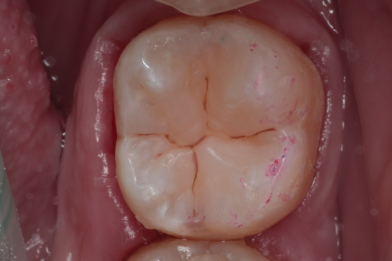

При профилактическом осмотре полости рта у пациента был выявлен кариес 2.6 зуба. Было произведено лечение кариеса с восстановлением анатомической формы зуба.

Бояринов Сергей Эдуардович -